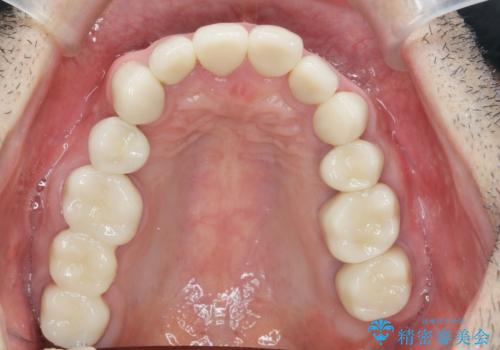

矯正治療を絡めた総合的な治療をお行なったことで、理想的な咬合関係を確立し安定した噛み合わせで仕上げることができました。

また歯周外科を行うことで歯ぐきの腫れを改善し、清掃性を高めています。